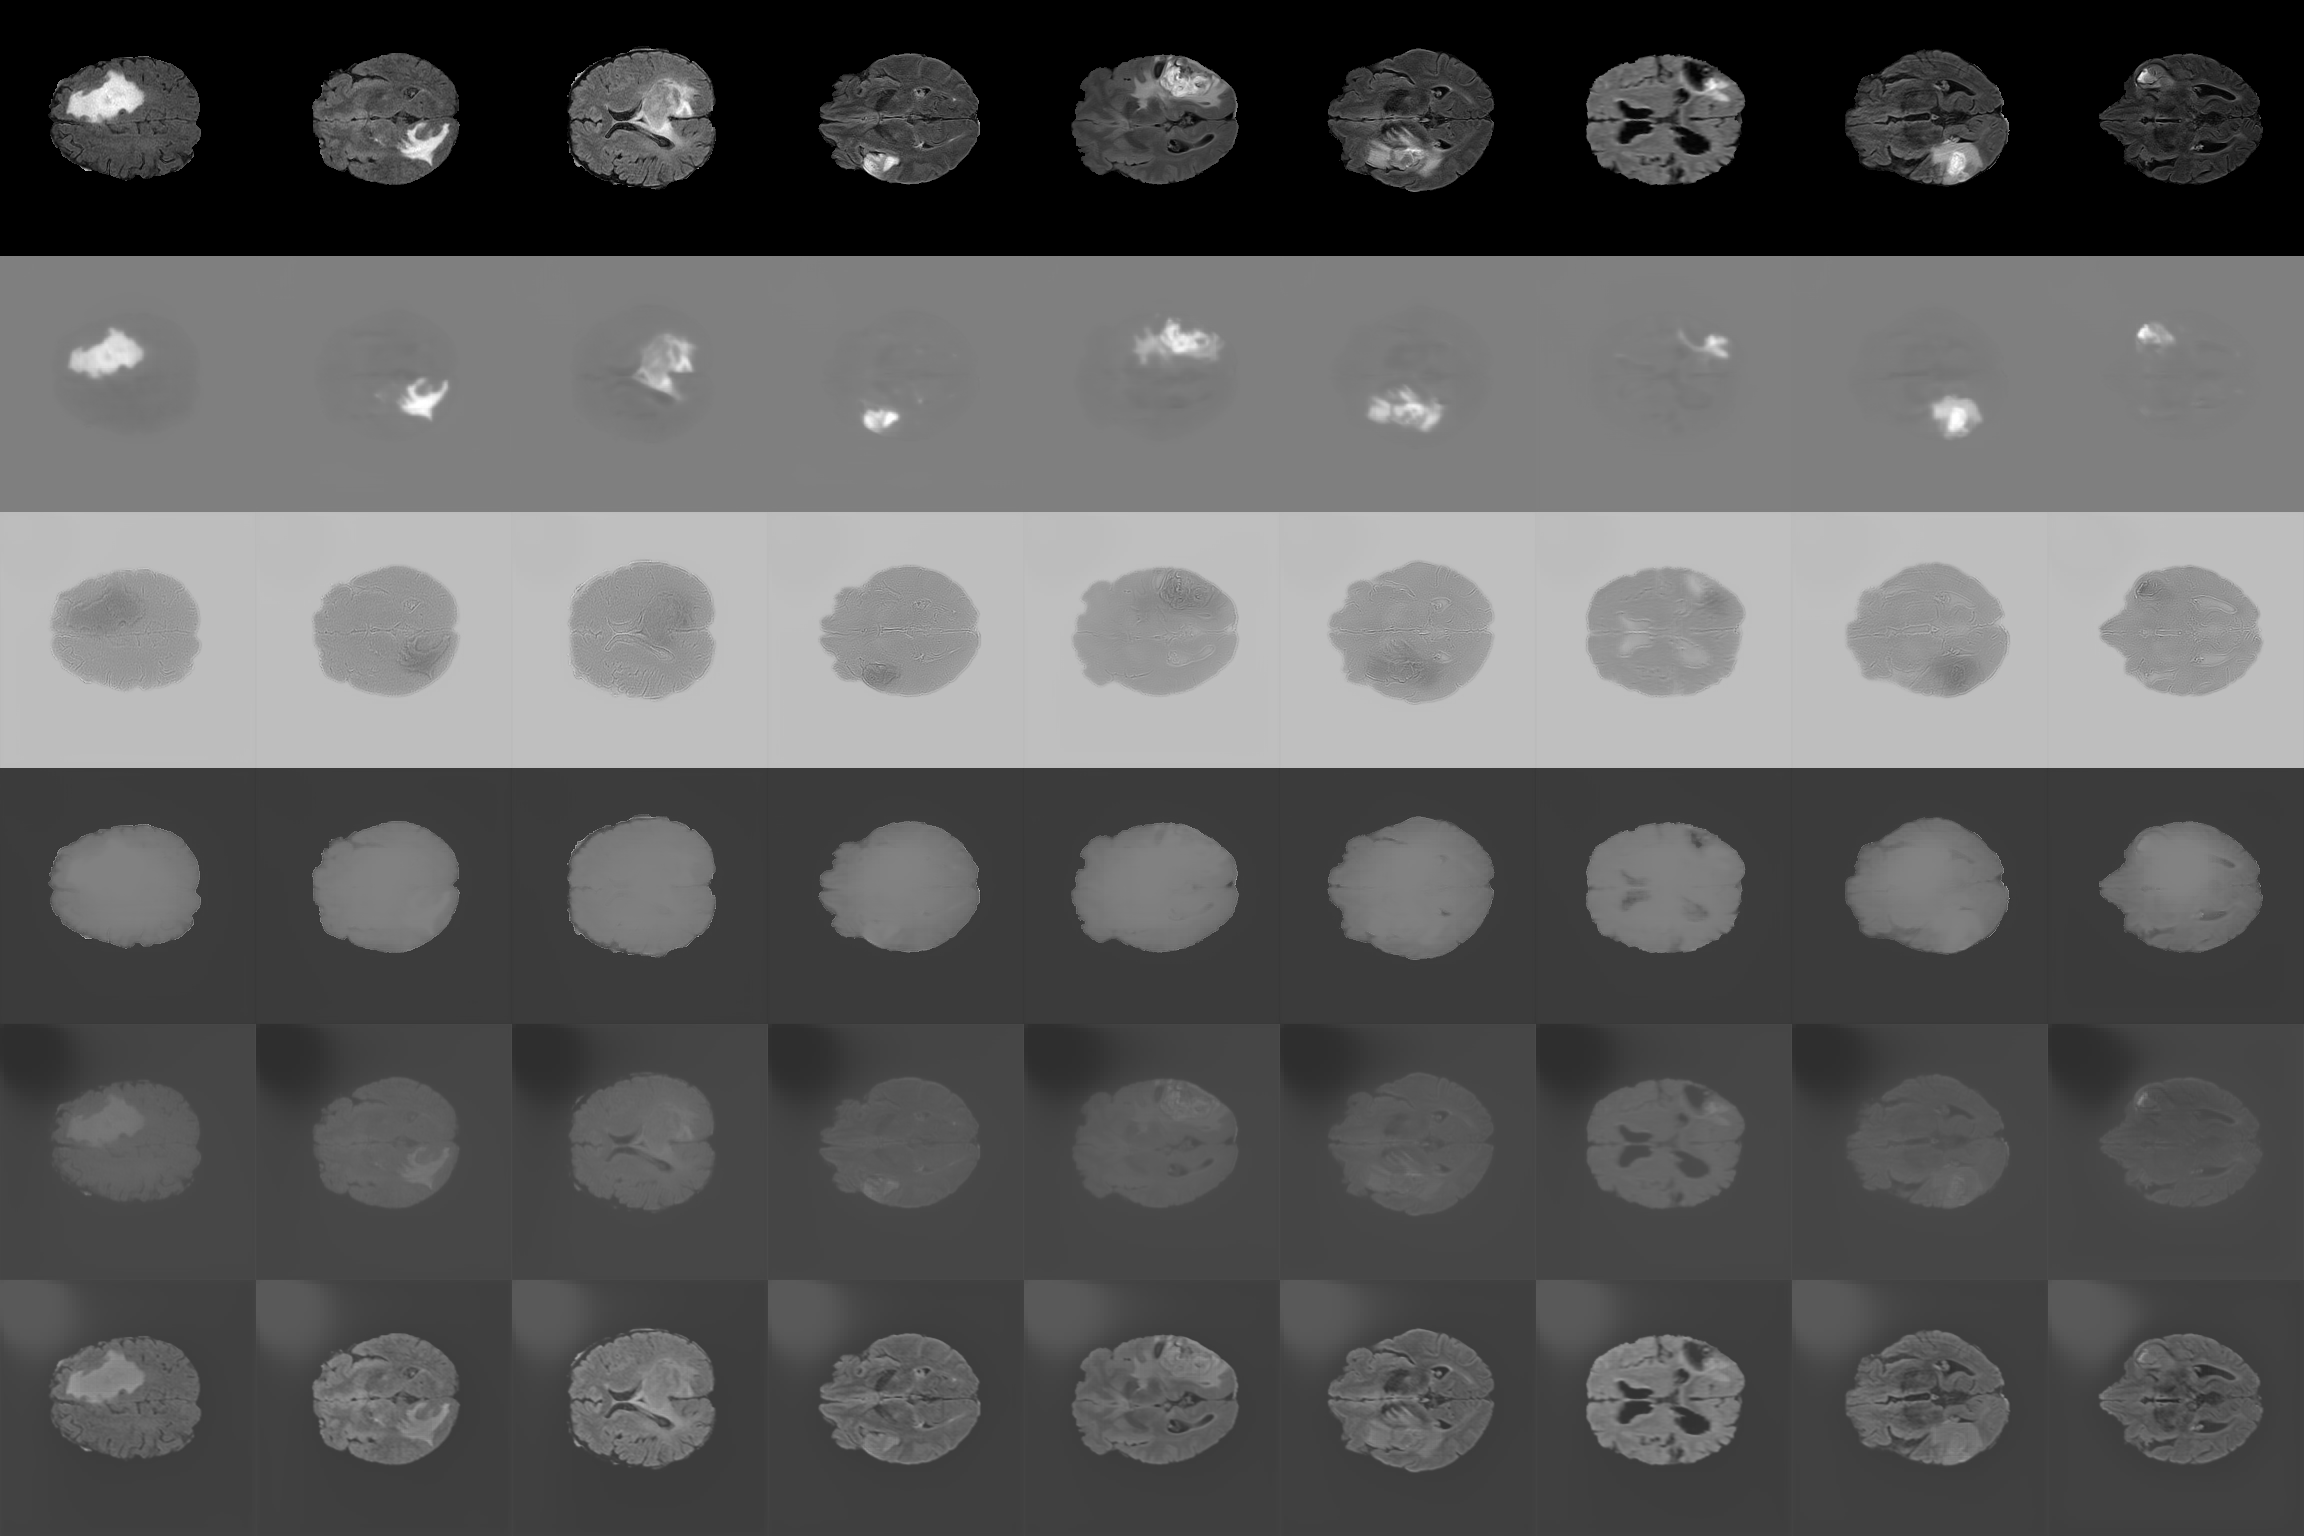

4.2 Anomaly Detection

We now evaluate the performance of our proposed algorithm for the task of anomaly detection. This task is a special case of identifying differences between classes, with one class being defined as normal and the other as abnormal. The objective is to identify the factor that causes the image to be classified as abnormal. This task is commonly utilized for detecting abnormalities in medical imaging, such as tumors or fractures in MRI, CT or X-ray scans. In these scenarios, an image containing a pathology would be considered abnormal, in comparison to a healthy image (normal). To evaluate the algorithm’s performance in this task, we utilized the BraTS dataset [20]. It contains magnetic resonance imaging (MRI) scans of the brain with and without tumors. This dataset is widely used in the literature to demonstrate the performance of various methods in detecting tumors. However, it is important to note that we did not utilize the labeled information of the tumors themselves, but rather identified them based on the general label of the presence or absence of a tumor in the image. Therefore, we expect to observe tumors in the first branch 6, which contains the information on the identity of the class, when comparing images with and without tumors.

Refer to captionxorigsubscript𝑥𝑜𝑟𝑖𝑔x_{orig}ψ1subscript𝜓1\psi_{1}ψ2subscript𝜓2\psi_{2}ψ3subscript𝜓3\psi_{3}ψ4subscript𝜓4\psi_{4}ψ5subscript𝜓5\psi_{5}

Figure 6: Finding tumors results